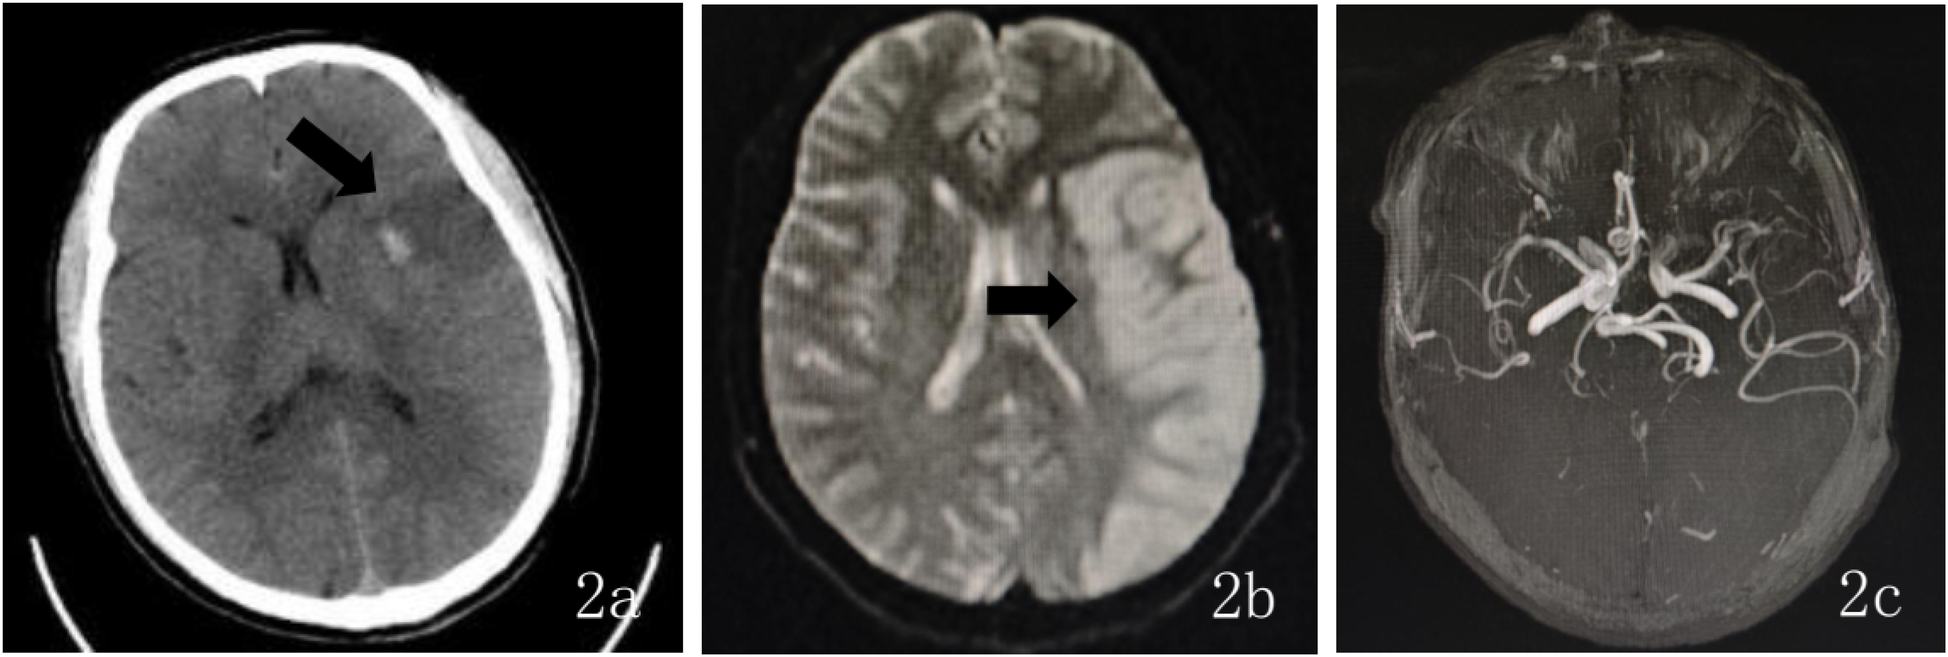

Upon admission, the patient had a temperature of 36.8 °C, heart rate of 75 beats per min, respiratory rate of 18 breaths per min, and blood pressure of 125/75 mmHg. The patient exhibited clouded consciousness, dysarthria, and irrelevant responses to questions. Examination revealed intact facial sensation bilaterally, with a shallow right nasolabial fold, accompanied by dysarthria and hoarseness. The tongue deviated to the right, and muscle strength in the right limbs was graded 2/5, with normal muscle tone and negative bilateral Babinski signs. The National Institutes of Health Stroke Scale (NIHSS) score was 15 (consciousness: 4, facial palsy: 1, right upper limb: 3, right lower limb: 3, language: 2, dysarthria: 2). The mRS score was 4 at the time of initial medical assessment, compared to a pre-stroke mRS score of 0. Laboratory tests showed uric acid 474.00 µmol/L, magnesium 2.33 mmol/L, and bicarbonate 16.20 mmol/L. Thromboelastogram revealed reaction time (R) of 1.0 min, coagulation time (K) of 0.0 min, angle of 26.3 degrees, maximum amplitude (MA) of 9.9 mm, coagulation index (CI) of −5.2 min, and G of 0.5 d/sc. No significant abnormalities were found in the complete blood count, coagulation profile, or immune function tests. Emergency cranial CT revealed a patchy, slightly hypodense area in the left temporoparietal lobe (Figure 1a), suggesting an acute-phase cerebral infarction. Subsequently, at 02:30 digital subtraction angiography (DSA) was performed using the Sellinger technique with right femoral artery puncture, placement of a 5F arterial sheath, and systemic heparinization. A 5F curved catheter was used for aortic arch and full-brain angiography. The DSA revealed a Type III aortic arch, “string of beads” appearance in the right internal carotid artery, and a dissection aneurysm in the C1 segment (Figure 1b). Additionally, the left internal carotid artery showed occlusion at its origin, with a modified Thrombolysis in Cerebral Infarction (mTICI) grade 0 (Figure 1c), and generalized cerebral vascular tortuosity and sclerosis. DSA demonstrated segmental, string-of-beads changes with local dilatation and eccentric stenosis in the extracranial right ICA, accompanied by a dissection aneurysm but without evident wall plaque, consistent with the imaging features of FMD. Considering the absence of fever, elevated inflammatory markers, anemia, non-tubular stenosis, clinical manifestations of hereditary connective tissue diseases associated with aneurysms and dissections, and a family history of aneurysms or dissections, combined with evidence of FMD, the condition was differentiated from large-vessel vasculitis, spontaneous artery dissection, and hereditary connective tissue diseases. Based on a comprehensive evaluation of preoperative imaging and the patient's clinical history, the final diagnosis was internal carotid artery fibromuscular dysplasia and left ICA occlusion.

Figure 1

Figure 1. (a) Preoperative (October 17, 2024) head CT findings: axial CT shows a large area of slightly low-density lesions in the left temporal-parietal lobe. (b) Intraoperative DSA findings during endovascular therapy: The lateral DSA demonstrates a “string of beads” appearance in the right ICA, accompanied by a dissecting aneurysm in the C1 segment. (c) Lateral DSA shows occlusion at the origin of the left ICA. (d) Intraoperative lateral DSA shows recanalization of the left ICA. (e) Intraoperative lateral DSA revealed areas of alternating stenosis and dilatation in the left ICA, with a dissecting aneurysm in the C1 segment. (f) Intraoperative anteroposterior DSA shows “string of beads” changes in the left ICA at the C1 segment, with restored distal blood flow.

After providing a detailed explanation of the patient's condition and treatment plan to the family, they agreed to proceed with intra-arterial endovascular thrombectomy. During the procedure, intravenous dexmedetomidine was continuously infused. The 5F arterial sheath was subsequently replaced with an 8F sheath, and the 8F guide catheter was positioned at the origin of the left ICA. A 6F intracranial support catheter was successfully navigated to the occlusion site, where negative pressure aspiration was performed. After the support catheter was removed, a significant amount of thrombus was successfully extracted. Immediate angiography revealed patency of the left ICA (Figure 1d), with alternating stenosis and dilatation in the left ICA and a dissection aneurysm in the C1 segment (Figure 1e). Tirofiban 10 ml was slowly injected into the artery, and a continuous intravenous infusion was maintained. After 15 min of observation, follow-up angiography showed restoration of distal blood flow with a mTICI grade 3 (Figure 1f). The procedure was successfully completed, and the patient's vital signs remained stable throughout the surgery. Postoperatively, the sheath was removed, a closure device was applied to seal the puncture site, and the wound was compressed for 15 min with no active bleeding. Finally, the wound was dressed with a sterile bandage, and the patient was safely transported back to the Intensive Care Unit (ICU).